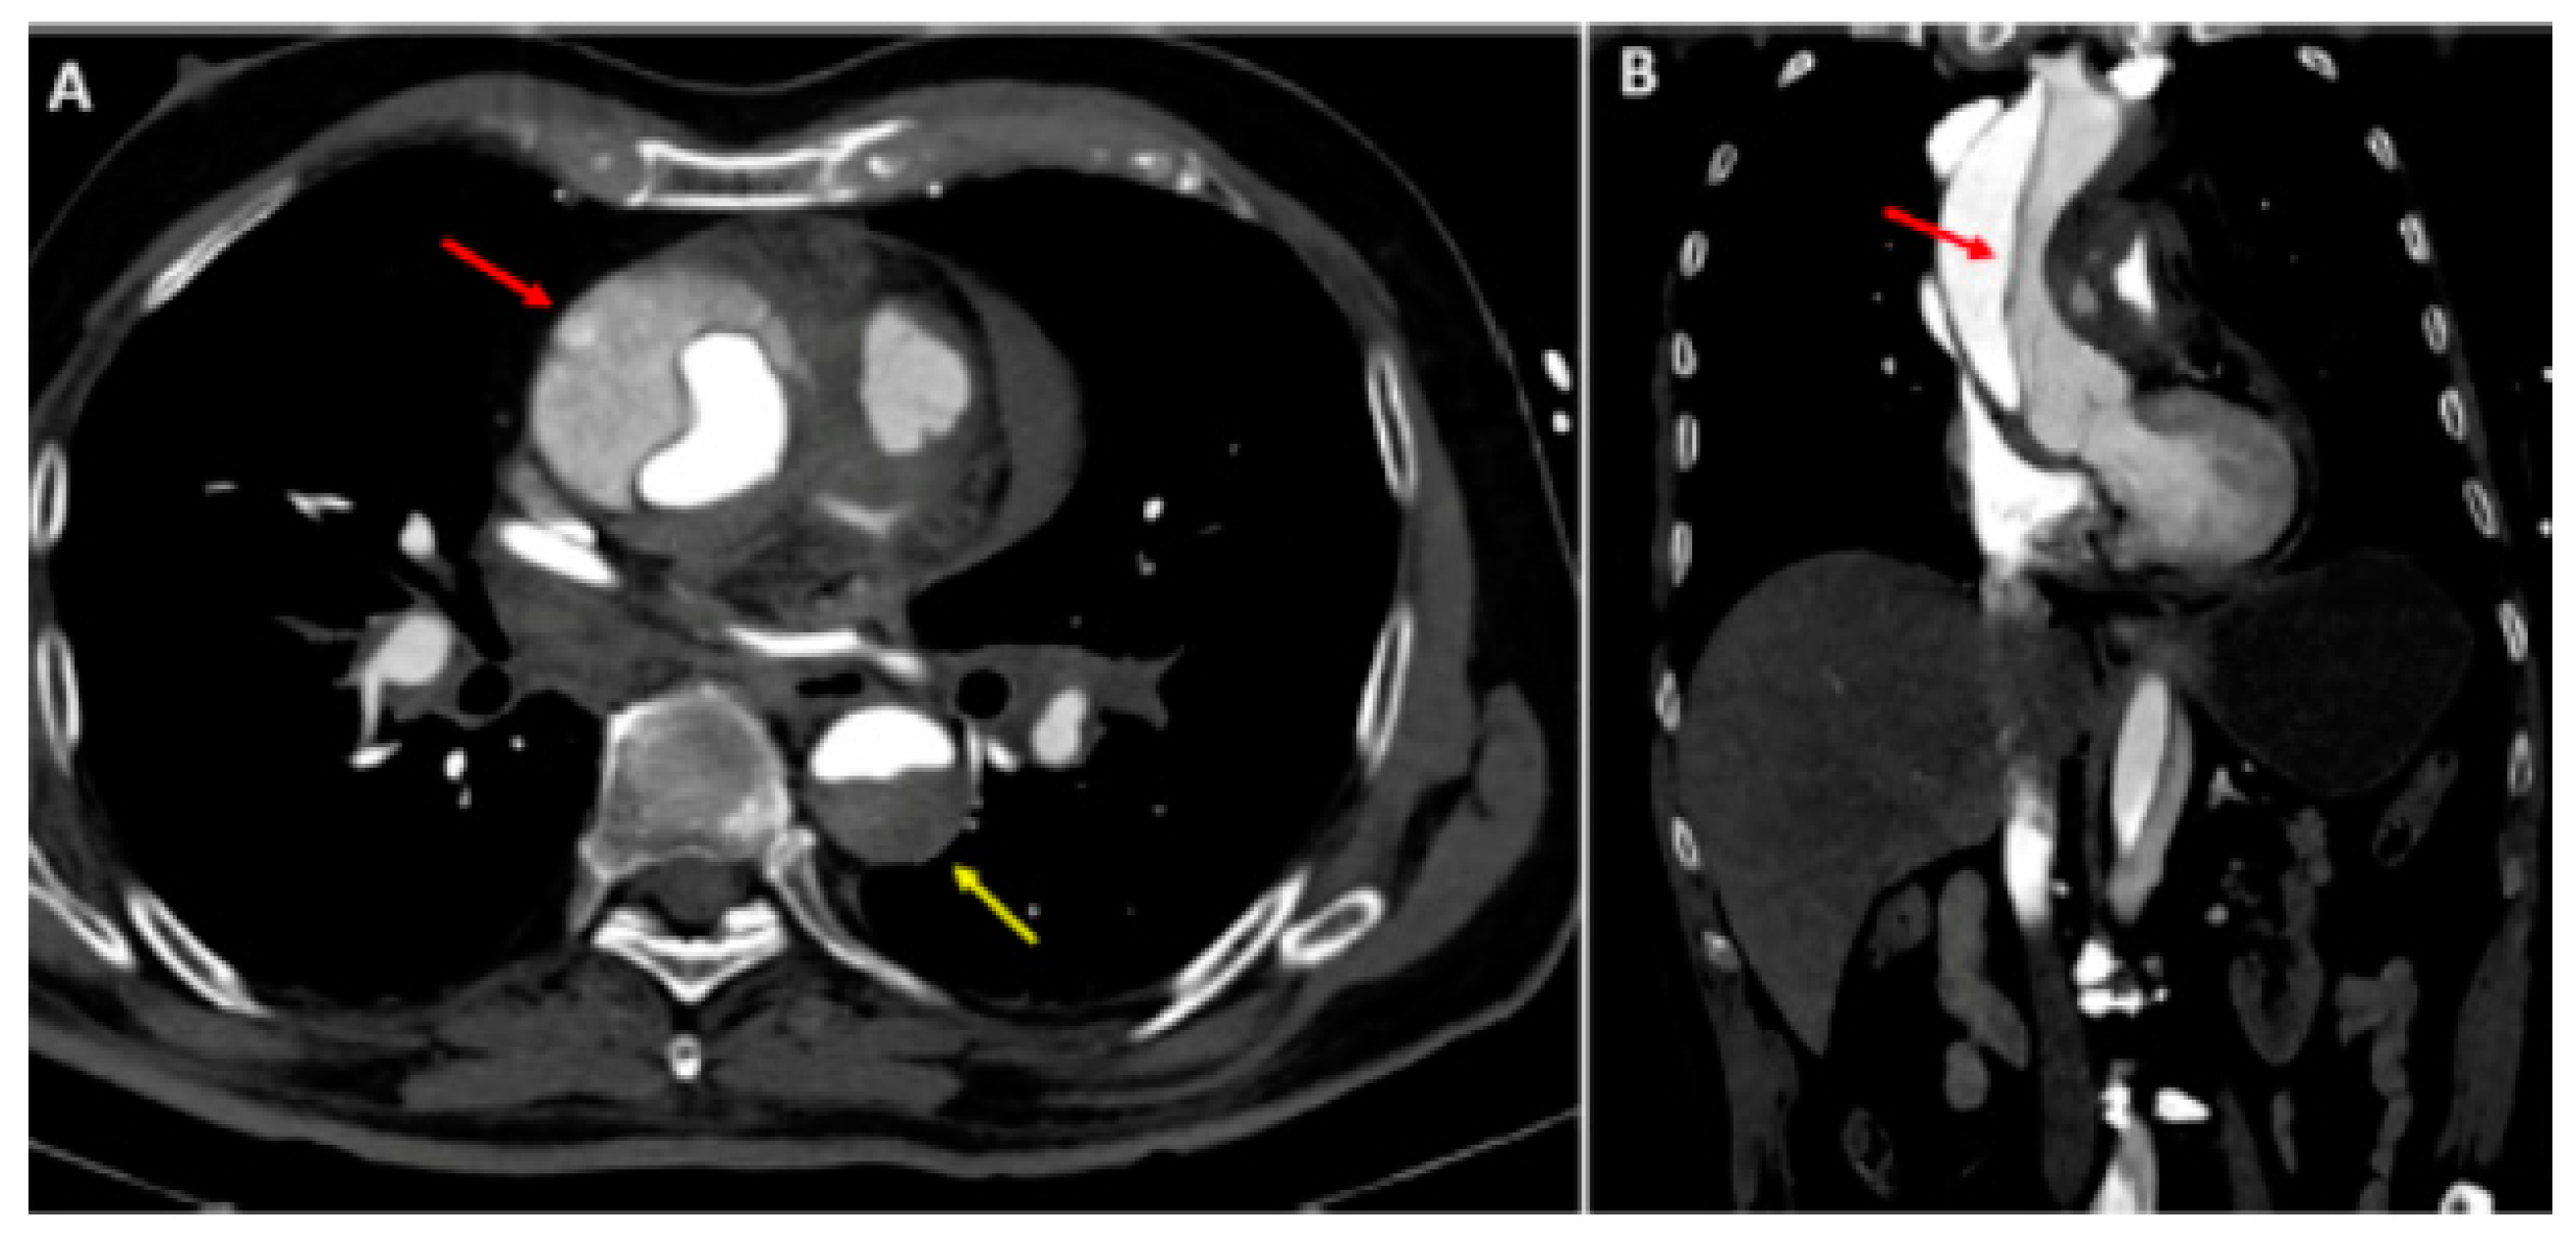

Figure 2.

Type A aortic dissection: (A) Computed tomography axial view. Ascending aorta (red arrow) and descending aorta (yellow arrow) dissection; (B) dissection extending into the right subclavian artery (sagittal view). Reprinted/adapted with permission from Ref. [18]. Copyright year 2021, with permission from Elsevier.